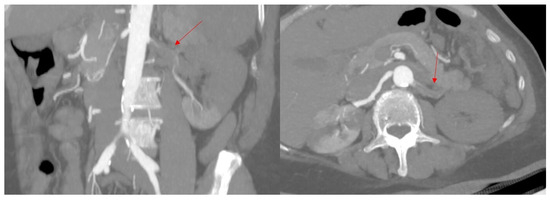

2. Case Presentation